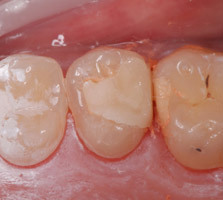

- Cas 4 : 1 prémolaire supérieure - 1 séance de 75 minutes